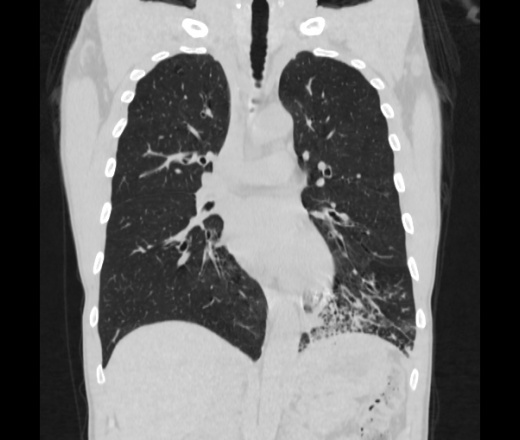

Мужчина пенсионного возраста. Цель назначения КТ ислючение зла в левом легком. Вижу тракционные бронхоэктазы с рубцовой эмфиземой по периферии, скорее всего БЭБ в стадии обострения. Дивертикулы трахеи. Выложил из за того что есть доля сомнения в отношении исключения зно3, немного смущают линии похожие на Керли.

Единственно, не сказал бы, что это тракционные бронхоэктазы, ну, и про линии Керли не вполне понял.

Ну да. Выразился не правильно. На фоне легочного рисунка усиленного линии похожие на септальные, не знаю как называются, при интерстиц.отеке похожие

На мой взгляд, это не главное, указал бы в описании - локально утолщен междольковый интерстиций, и всё